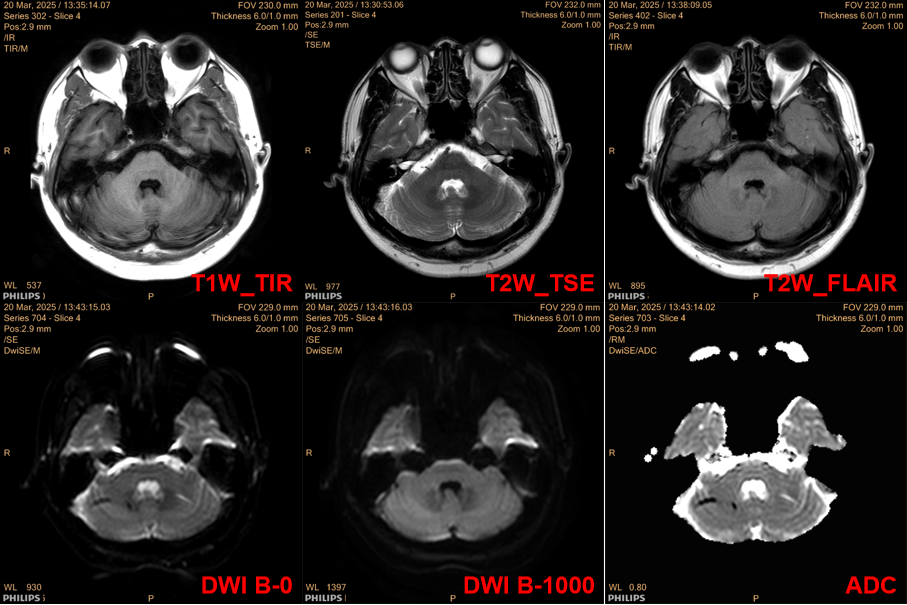

1. Case DescriptionPatient A, male, 43 years old, has had occipital pain for more than two months, and thus underwent a brain MRI plain scan + DWI + MRA, with results as shown in the images:

The plain scan report indicates: high signal in the white matter (Fazekas grade I), suspicious low signal in the right cerebellar hemisphere on T2WI with abnormal ADC signal, further examination is recommended; TOF-MRA suggests slight narrowing of the left anterior cerebral artery A1 segment;Therefore, an MRI enhancement scan was additionally ordered; after the examination, no obvious abnormal enhancement was observed, with results as shown in the images:

After completing the examination, the diagnosis and clinical team felt confused about the results; thus, they consulted the author regarding the cause.2. Cause Analysis1.Reasons and Identification of Abnormal Image InformationThe issue was discovered during the plain scan, so we must first look at the images: from the ADC map, we can see significant diffusion restriction in the right cerebellar hemisphere; however, upon reviewing other weighted images, no corresponding abnormalities were found in that area. Where does the description of low signal on T2WI in the report come from? Upon reviewing the report description, I found that “no abnormal high signal was seen in the DWI sequence, and low signal was observed in the right cerebellar hemisphere on b=0 and ADC map with chaotic tubular and patchy low signals”; combined with the actual image performance, we can infer that the report physician’s description of the abnormal T2WI signal was based on the B0 image.As we know, the B0 image of the DWI sequence is equivalent to a T2 star fat-suppressed weighted comparison, which is more sensitive to the Mxy phase acceleration loss caused by B0 field inhomogeneity and is often used to assist in judging fat signals or ferromagnetic substances; ADC reflects the differences in the diffusion coefficients of tissues and supports semi-quantitative measurements; however, it is not directly obtained from the device scanning but is calculated through fitting the signal attenuation of different B values in a single DWI scan; the accuracy and reliability of the ADC value are directly related to the image quality of the DWI sequence: when the original DWI data is affected by other factors, it will inevitably lead to unreliable ADC values.Observing the DWI images, we find that B0 has a low signal, while B1000 has an equal signal, leading to the following interpretations of the image information: ① B0 has a low signal, possible reasons include deposition of ferromagnetic substances, signal suppression of fat components, or the flow void effect of large blood vessels; ② The high B value image has an equal signal, while the B0 image has a low signal, indicating the presence of T2 signal cancellation, and that area is highly restricted in diffusion, while excluding the possibility of flow void effects.Regarding information ①, the possibility of fat components no longer needs to be considered (no corresponding high signal was seen on the T1_FLAIR sequence); as for the flow void effect of large blood vessels, it must be a high signal in TOF-MRA and enhancement scans, and some flow void signals should be observable in conventional T2WI images; however, the interpretation of other sequences does not confirm this; for information ②, T2 cancellation effects are common in vasogenic edema, which inevitably leads to an increase in local water molecule content, yet no signal abnormalities were observed in the corresponding FLAIR sequence, and no abnormal enhancement was seen in the enhancement scan, indicating that the blood-brain barrier in this area was not compromised.Thus, we must consider other possibilities for the abnormality in the original DWI sequence data: if we only interpret the information from the cranial MRI plain scan + MRA + enhancement scan, then there are no obvious abnormalities in the right cerebellar hemisphere; while observing the B value images alone, the information from B1000 matches that of other examinations; if the B0 data has artifacts, it can explain the series of abnormalities and contradictions mentioned above; when B0 has a low signal and B1000 has an equal signal, the calculated ADC will inevitably indicate “restricted diffusion”, but this information is misleading due to B0 artifacts, which can be traced back in the information transmission chain.2. Such cases are not uncommonIn previous posts, I have discussed similar issues: since ADC is calculated from the original DWI data at different B values, when the original data has issues, it will inevitably lead to a decrease in the accuracy of ADC data; in previous posts, the factors causing inaccurate ADC values were due to spatial registration differences, while in this case, the factor causing abnormal ADC values was B0 image artifacts.